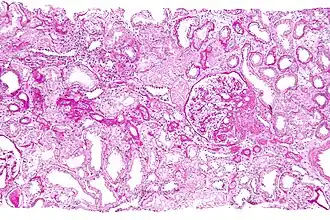

Micrograph showing a renal core biopsy. PAS stain.